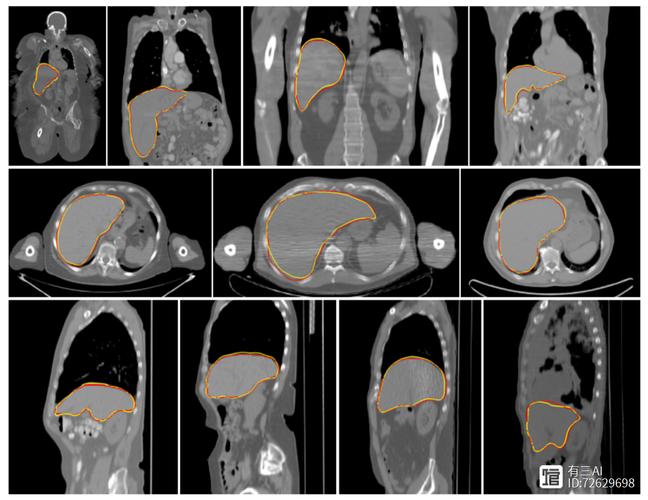

- 医疗与军事图像安全:在传输病人的CT或MRI影像时,可以将患者ID、诊断结果等敏感信息隐藏在图像本身中,实现“图像与信息”的绑定传输,防止信息泄露或错位。